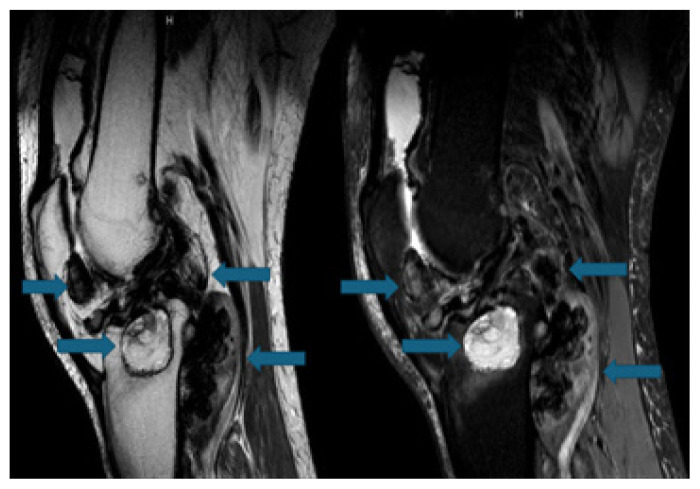

Pigmented Villonodular Synovitis: A Critical Review.